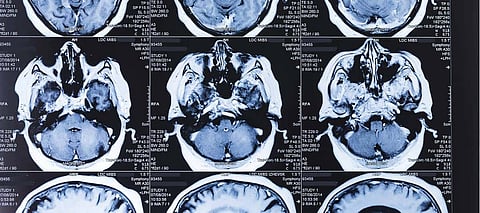

Since the sector is overwhelmed by impecunious research, the latest findings are based on a few numbers of studies. And the researchers found one of the burgeoning applications is the use of AI in medical images, a field relies on Deep Learning, wherein a series of labelled images are fed into algorithms that pull-out features within them and learn how to classify similar images.

This approach has shown promise in disease treatment, from eye conditions to cancer. However, responding to questions on how such deep learning systems measure up to human skills, researchers conducted the first comprehensive review of published studies on the issue that revealed humans and machine are on a par.

Afterward, the team pooled up the most promising results from each of the 14 studies that found deep learning systems correctly detected a disease state 87% of the time, compared with 86% for healthcare professionals, as well as correctly gave the all-clear 93% of the time that outperformed the human experts with 91%.

With these outcomes, Denniston is very optimistic about the potential of AI in healthcare, with saying such deep learning systems could perform as a diagnostic tool and assist in tackling the backlog of scans and images. In the same context, Liu said such systems could prove useful in places which lack experts to interpret images. It would be significant to leverage deep learning systems in clinical trials to weigh, whether patient outcomes improved compared with current practices.